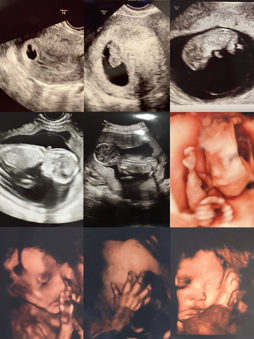

さて、私事ではございますが、近日中に我が子が産まれてくる予定です。(投稿される頃には分娩に至っている可能性もありますが…)写真は我が子の超音波画像で、初期研修医時代に自分で検査して保存しておいたものも含まれます。診療に影響を与えないように平常心で過ごそうとしておりましたが、ここ数週間は心がそわそわと落ち着かない状態です。その理由は、単にお産が近づいているだけではなく、名前がまだ決まっていない焦りもありますが、考えるに父親になることへの重圧によるものです。産婦人科病棟では日々新たな命の誕生の場面に立ち合いますが、僕は新たな家族の誕生を一緒にお祝いする気持ちとともに、近頃は、この子がどう育ち成長していくのか、家族にどう影響を与えるのか、どのような家族を形成していくのか、と思いを巡らせるようになりました。そして日常的にすべてのお母さん・お父さんに対して尊敬の念を抱くようになりました。親になることは特別なことです。家族のかたちを大事にできる医師であるべく、親になってなお一層責任感を持って臨んで参ります。少し気は早いですが、周囲の皆様には公私ともにご指導・ご鞭撻のほどよろしくお願い申し上げます。